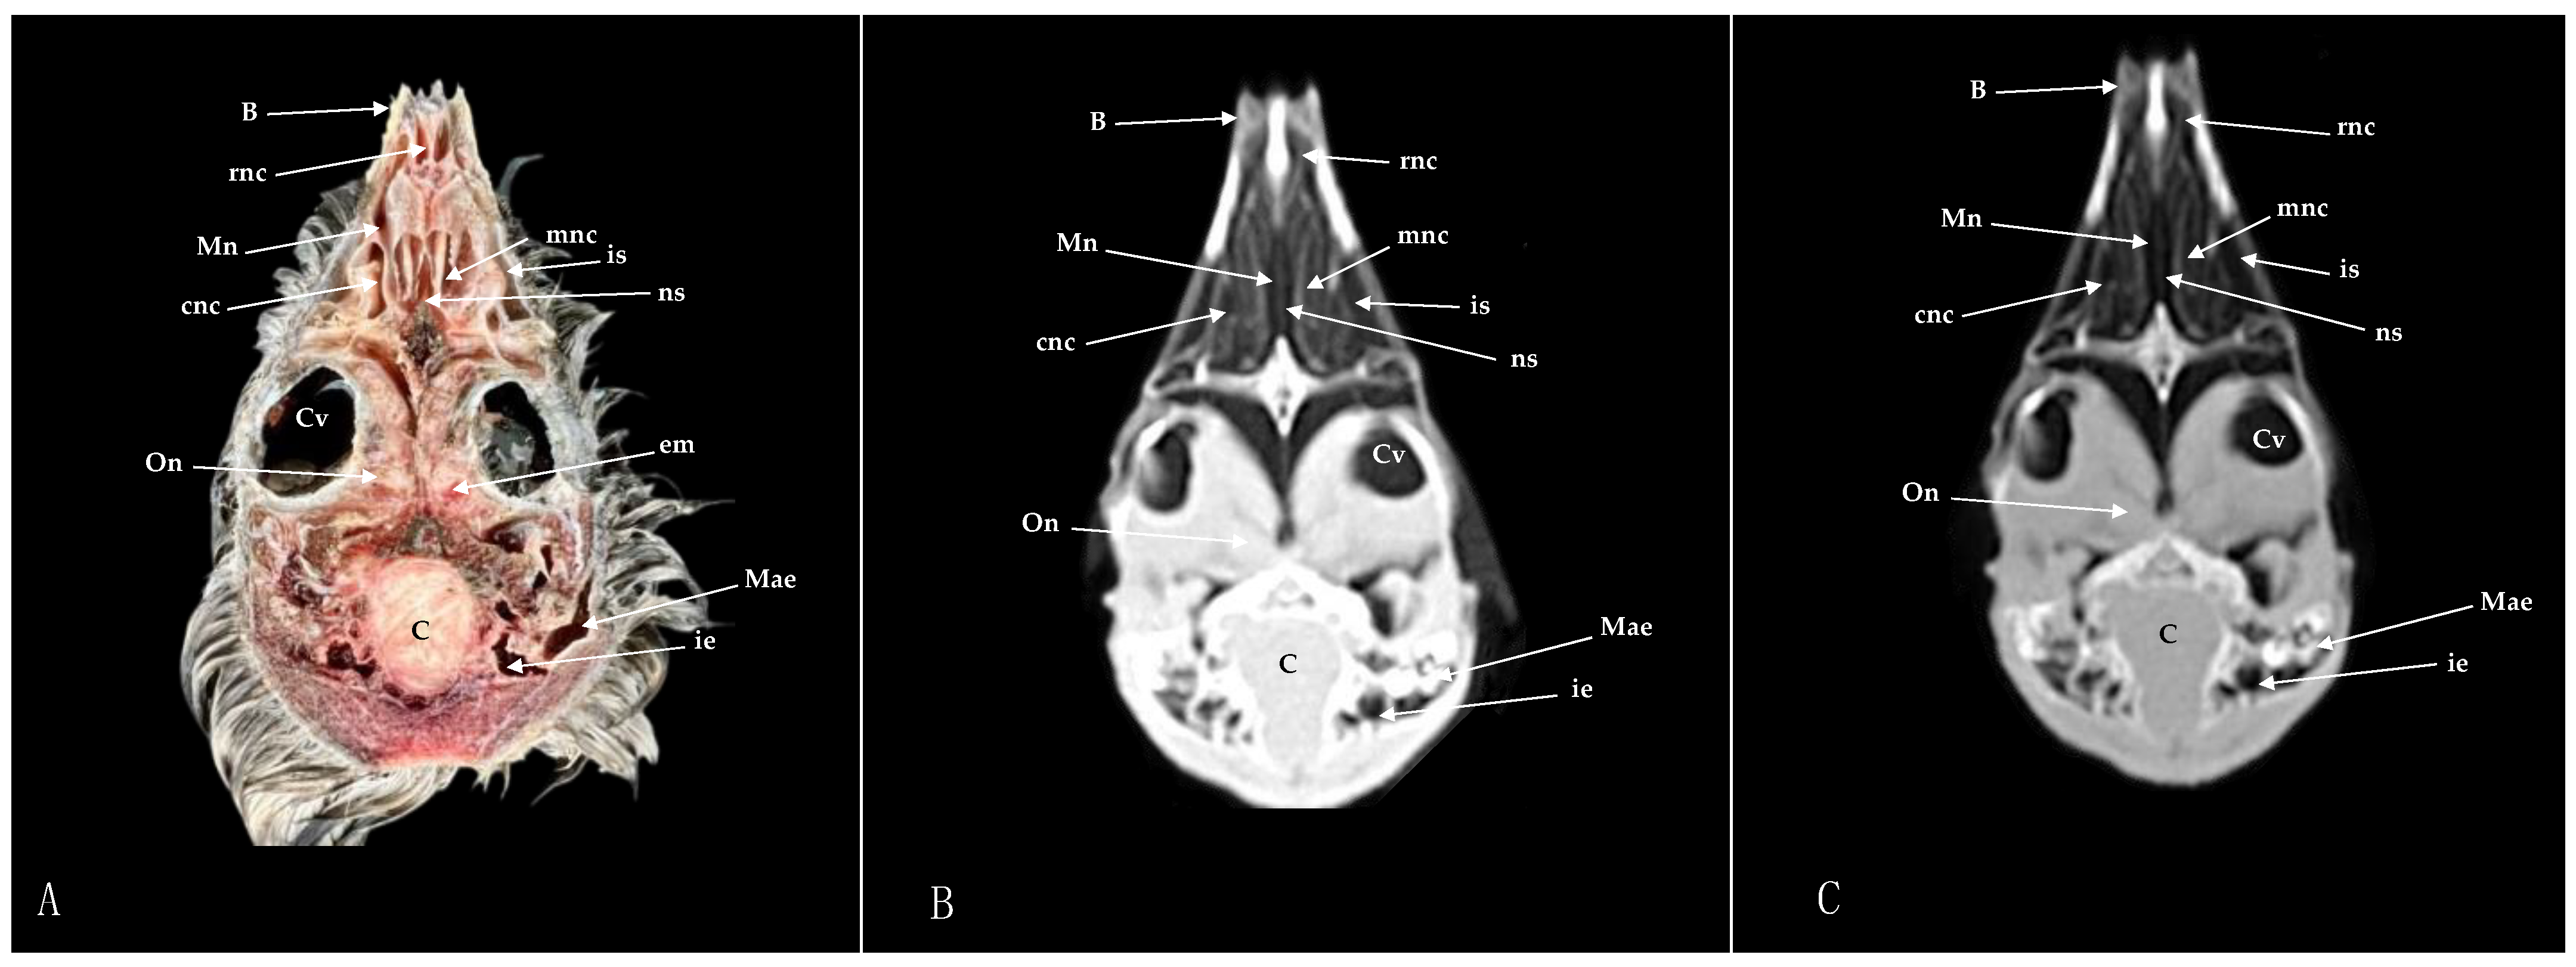

3.1. Anatomical Sections

3.2. Computed Tomography (CT)